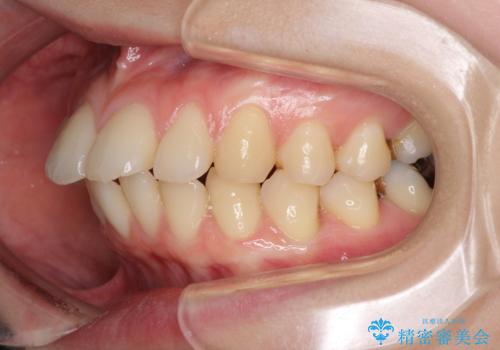

- 口元の突出感と口の閉じにくさを気にして来院された患者様です。

上下左右第一小臼歯4本を抜歯し、ワイヤー装置にて口元を引っ込めるよう矯正治療を行うこととしました。